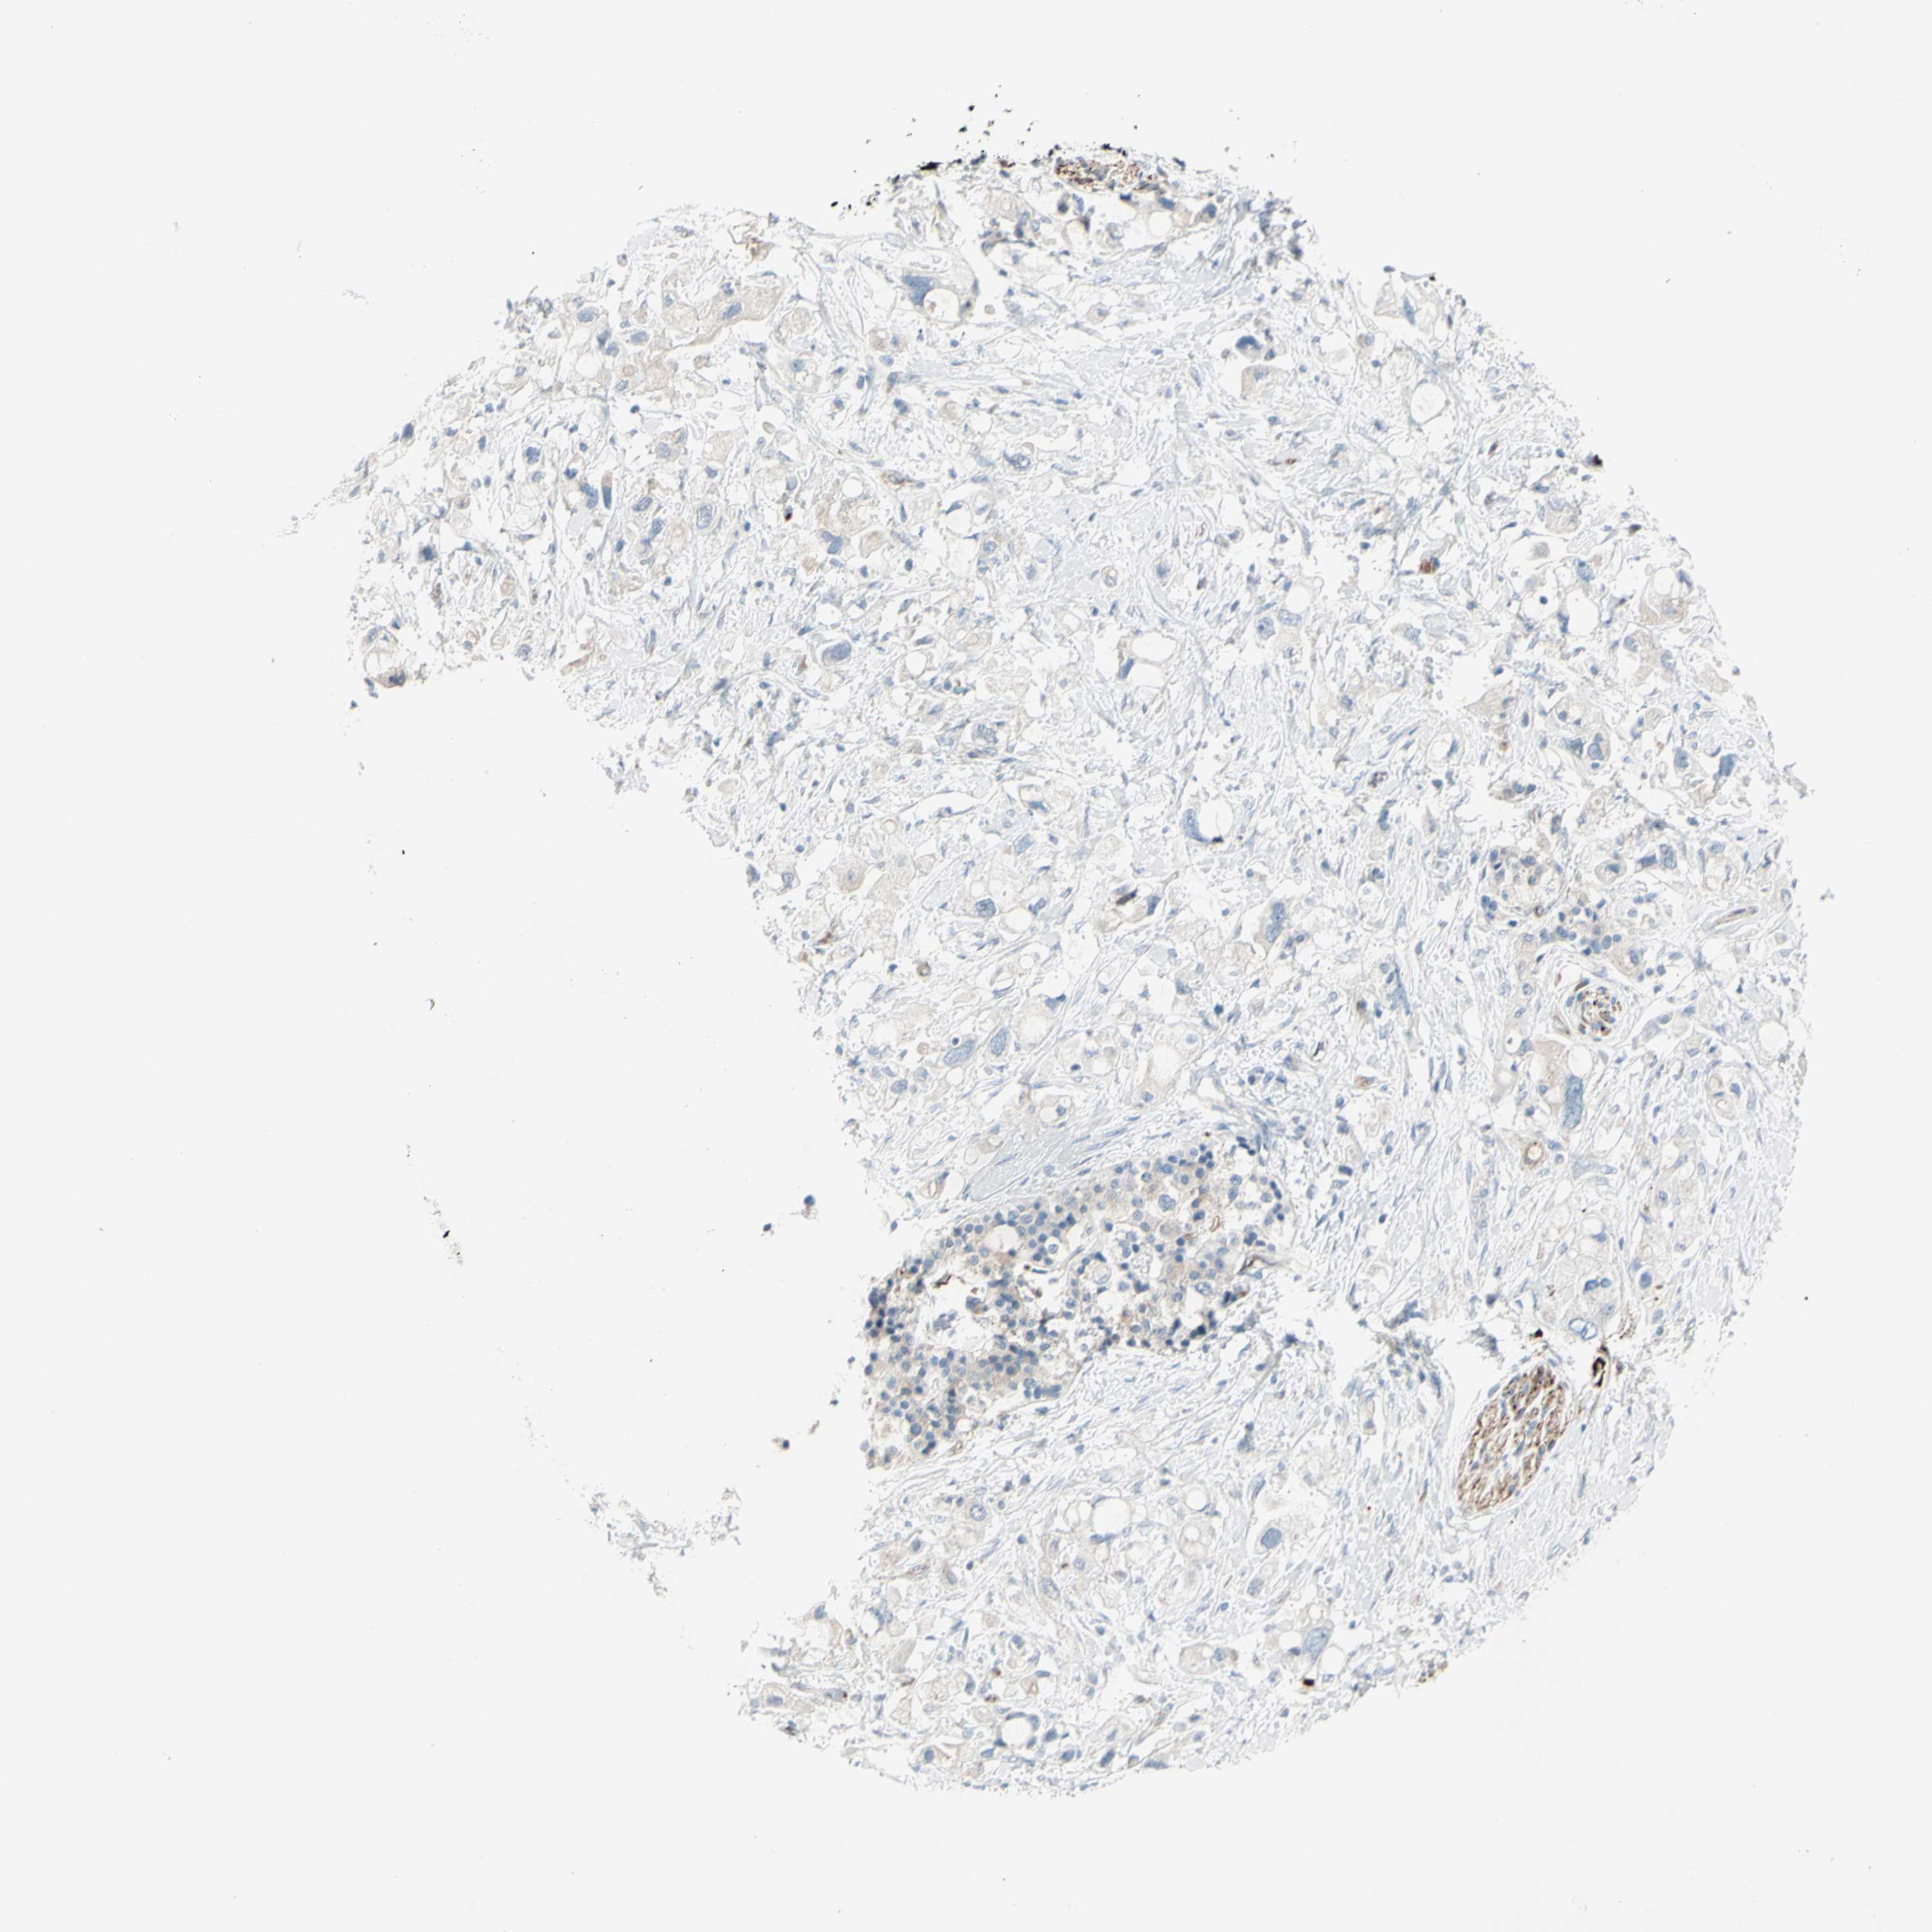

PANCREATIC CANCER - Protein expressioni

A mouse-over function shows sample information and annotation data. Click on an image to view it in a full screen mode. Samples can be filtered based on level of antibody staining by selecting one or several of the following categories: high, medium, low and not detected. The assay and annotation is described here.

Note that samples used for immunohistochemistry by the Human Protein Atlas do not correspond to samples in the TCGA dataset.

Antibody stainingi

Antibody staining in the annotated cell types in the current human tissue is reported as not detected, low, medium, or high, based on conventional immunohistochemistry profiling in selected tissues. This score is based on the combination of the staining intensity and fraction of stained cells.

Each image is clickable and will lead to virtual microscopy that enables deeper exploration of all samples and also displays staining intensity scores, fraction scores and subcellular localization as well as patient and tissue information for each sample.

Antibody HPA010668

Antibody CAB025490

Staining

High

Medium

Low

Not detected

Intensity

Strong

Moderate

Weak

Negative

Quantity

>75%

75%-25%

<25%

None

Location

Nuclear

Cytoplasmic/membranous

Cytoplasmic/membranous,nuclear

Adenocarcinoma, NOS

Adenocarcinoma, metastatic, NOS